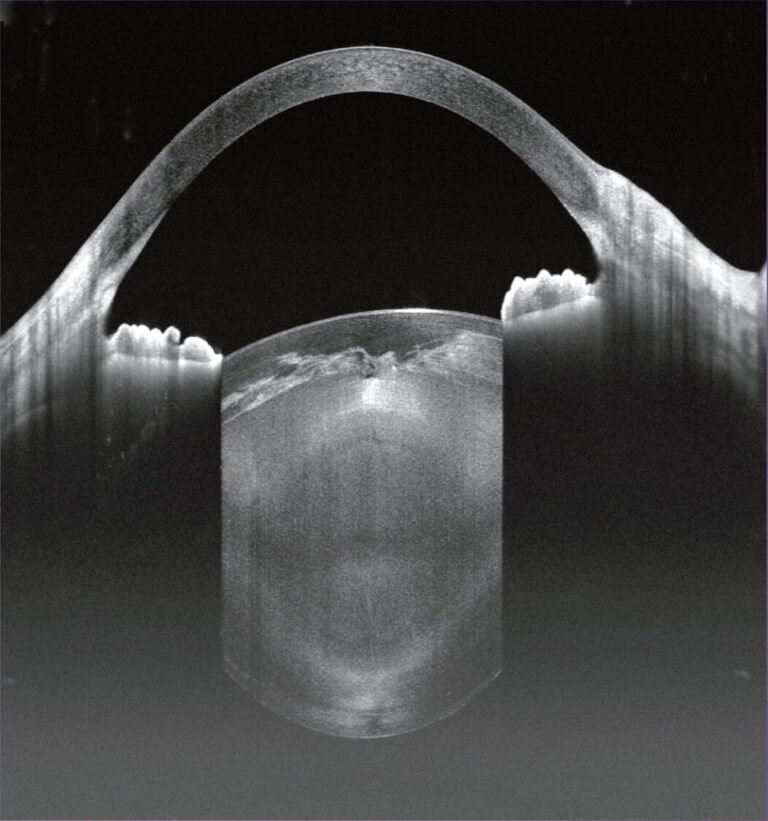

Voorste Oogsegment OCT

- Van epitheel tot achterste lenskapsel

- Scan van 24 mm tot 15 mm

- Cornea-mapping: pachymetrie-, epitheel- en stromadiktekarten

- Metingen van voorste oogsegment en AC-hoek

- Automatische identificatie van sclera-uitloper en hoekrecessie

- Enkelvoudige lijn, HD radiaal (8 lijnen) AS radiaal (72 lijnen)

3D Anterior Scan